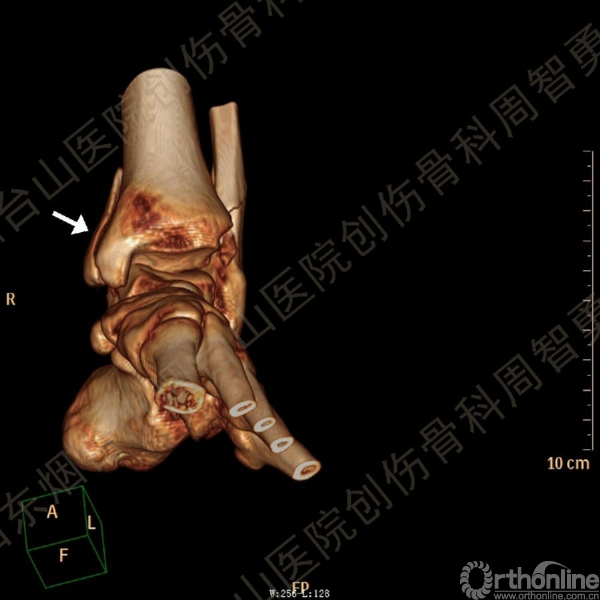

患者一般情况可,左踝关节肿胀,见皮下瘀斑,内、外、后侧有压痛,左踝关节主动运动受限,左足皮肤感觉、血供未见明显异常,左足趾各关节可主动运动。左踝关节正位X线片和CT重建示内踝内上方双层骨皮质影(图1a,c),CT示后侧骨折块分为后内侧骨折块和后外侧骨折块(图2a,b),后内侧骨折块累及内踝后丘,后丘骨折线呈冠状位(图2c),后内侧骨折块腹侧有向近端塌陷的小块骨软骨骨折块(图2d),CT也显示Chaput骨折块(图1c,2e)。

经典的后踝骨折发生于低能量旋转外力所致的踝关节骨折;标准pilon骨折见于高能量轴向暴力;而后侧pilon骨折是旋转外力和轴向暴力共同作用的结果,属于中等能量的损伤。踝关节骨折中的后踝骨折源自下胫腓后韧带的牵拉,骨折块位于后外侧,常为单一的三角形骨折块,大小从关节外片状骨折到累及胫骨远端关节面矢状径的40%(图4a)。后侧pilon骨折中的后侧骨折块较大,累及内踝后丘(三角韧带深层起点)在内的整个胫骨远端后侧,分为后内侧骨折块和后外侧骨折块,后内侧骨折块腹侧有向近端塌陷的骨软骨骨折块(图4b)。后侧pilon骨折中的内踝骨折线并不是水平位而是冠状位,可合并内踝前丘骨折。后侧pilon骨折踝关节正位X线片示特异性的内踝内上方双层骨皮质影(图1a,c)。这是由于后内侧骨折块的骨折线延伸到胫骨远端骨骺和干骺端的内侧骨皮质,其移位后的边缘成像所致。水平位CT显示后侧骨折块分为后内侧骨折块和后外侧骨折块,矢状位CT示后内侧骨折块腹侧有向近端塌陷的骨软骨骨折块。

↑图 1c

图 1 术前左踝关节正侧位X线片和CT重建,箭头所示内踝内上方双层骨皮质影(a,c)

图 2 术前CT,显示后侧骨折块分为后内侧骨折块和后外侧骨折块(a,b),后内侧骨折块累及内踝后丘,后丘骨折线呈冠状位(c),箭头所示后内侧骨折块腹侧有向近端塌陷的小块骨软骨骨折块(d),Chaput骨折块(e)